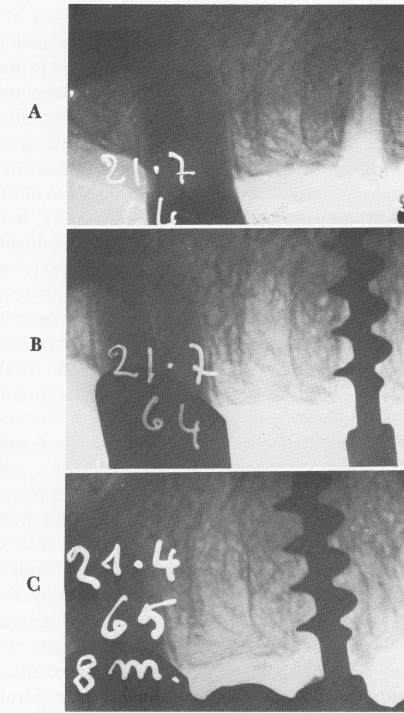

Fig. 5-24. Although the threads are at the alveolar crest, bone has grown around the lower portion of this well-stabilized Tramonte implant. A, Implantation soon after ex-traction of a root with a large granuloma; B, 1 month postoperatively; C, 6 months postoperatively. (From Tramonte, S.: L'implanto endosseo razionale, Milan, 1963.)